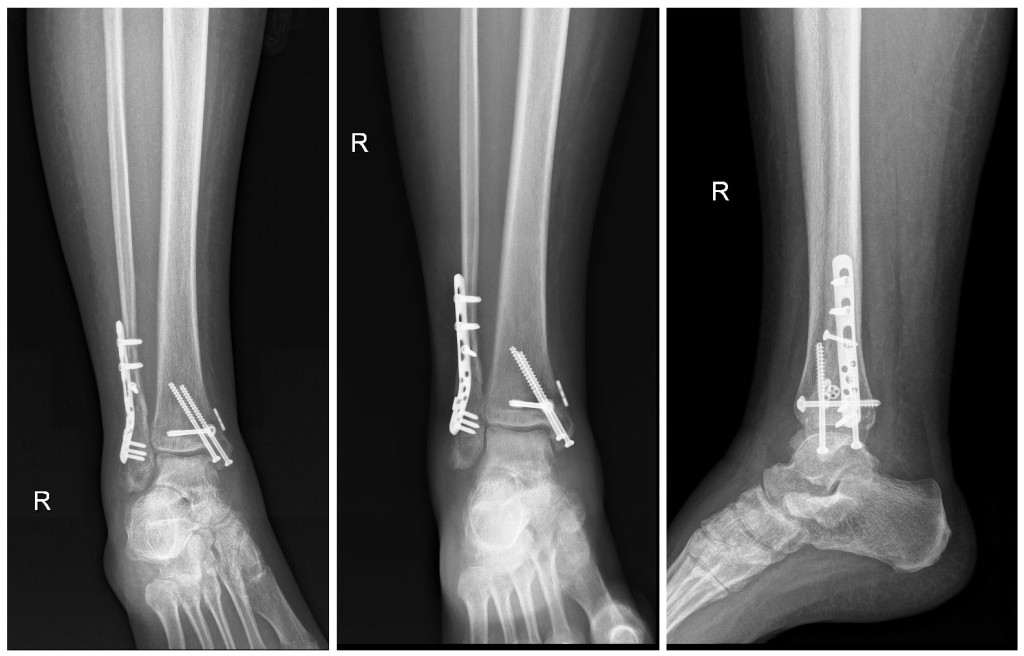

This week marks my wife's 6th month since the incident, and she is able to walk at this time.

She has 9 screws, a self tensioning fixator and a 6" metal plate in her ankle.

Here's what my wife's ankle looks like: